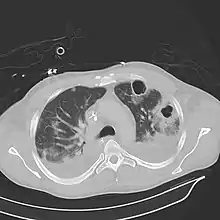

Computed tomography (CT) scan of chest showing bilateral pneumonia with abscesses, effusions, and caverns. 37-year-old male.